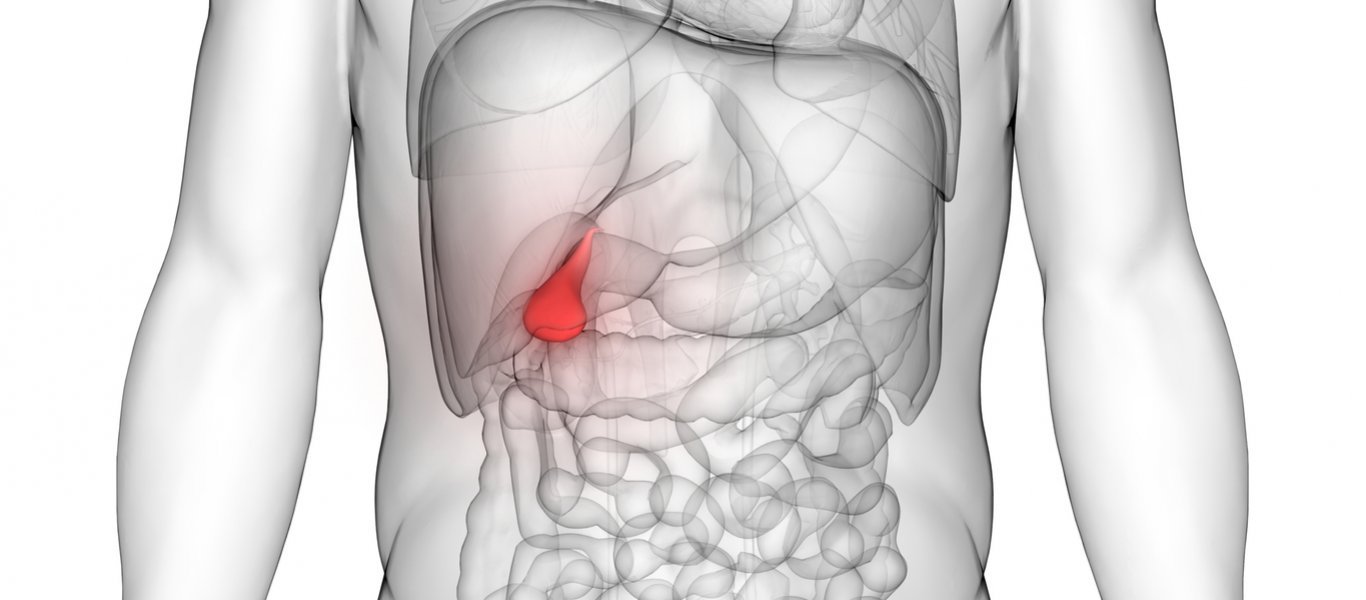

Οι πολύποδες της χοληδόχου κύστης είναι ανωμαλίες που αναπτύσσονται στο εσωτερικό τοίχωμά της.

Στους περισσότερους ασθενείς, ο εντοπισμός τους είναι ένα τυχαίο εύρημα ενός τυπικού υπερηχογραφήματος στην κοιλιά ή ακόμα και μετά από χολοκυστεκτομή εξαιτίας χολολίθων.

Οι πολύποδες της χοληδόχου κύστης είναι κυρίως καλοήθεις. Μπορεί να είναι ψευδοπολύποδες, οι οποίοι δεν έχουν κακοήθη πιθανότητα και δεν απαιτούν καμία παρακολούθηση ή παρέμβαση, ή αδενώματα.

Υπάρχουν επίσης και κακοήθεις πολύποδες, η έγκαιρη ανίχνευση και η αντιμετώπιση των οποίων είναι σημαντικές για τη θεραπεία και τη μακροχρόνια επιβίωση. Ο πρωταρχικός στόχος είναι η πρόληψη της ανάπτυξης του καρκίνου.

Μόνο το 5% θεωρείται ότι είναι πραγματικοί πολύποδες, που σημαίνει ότι είναι κακοήθεις ή έχουν πιθανότητα να είναι κακοήθεις.

Αυτοί απαιτούν χειρουργική αφαίρεση. Κατά κανόνα, η χολοκυστεκτομή συστήνεται για πολύποδες μεγέθους 10 mm και άνω, αν και αυτό το όριο μειώνεται όταν εντοπίζονται άλλοι παράγοντες κινδύνου. Είναι σημαντικό αυτοί να λαμβάνονται υπόψη ώστε να καταστεί ευχερέστερη η απόφαση αν θα διενεργηθεί χολοκυστεκτομή σε πολύποδες κάτω από τα 10 mm.

Συνήθως η παρουσία ενός πολύποδα ακόμα και μικρότερου των 10 mm προκαλεί ερωτηματικά, καθώς η μοναδική μελέτη που πραγματοποιήθηκε σε άτομα με πολύποδες 5-9 mm έχει δείξει ότι υπάρχουν περισσότερες πιθανότητες να είναι κακοήθης, όχι όμως τόσες που να επιβάλουν τη διενέργεια χολοκυστεκτομής, εάν δεν υπάρχουν κι άλλοι παράγοντες κινδύνου.

Η ηλικία είναι ένας τέτοιος παράγοντας, δεδομένου ότι οι περισσότερες κακοήθειες εμφανίζονται σε άτομα μεγαλύτερης ηλικίας. Μελέτη που εξέτασε την ηλικία ως παράγοντα κινδύνου για κακοήθεια σε πολύποδες κάτω από τα 10 mm διαπίστωσε ότι όταν ο ασθενής είναι άνω των 50 ετών η πιθανότητα καρκίνου ανέρχεται στο 20% περίπου και συνεπώς ο ασθενής πρέπει να υποβληθεί σε χολοκυστεκτομή.

Σε ασθενείς με συμπτώματα που οφείλονται σε χολόλιθους, η χολοκυστεκτομή είναι απαραίτητη. Δεδομένου, όμως, ότι έως 4 στα 5 άτομα με καρκίνο της χοληδόχου κύστης έχουν χολόλιθους, είναι προτιμότερη η αφαίρεση της κύστης.

Βέβαια, οι χολόλιθοι είναι πολύ συχνοί, ενώ ο συγκεκριμένος καρκίνος εξαιρετικά σπάνιος. Η συντριπτική πλειονότητα των ανθρώπων με πέτρες στα νεφρά δεν αναπτύσσουν ποτέ καρκίνο σε αυτήν.

Μελέτες έχουν δείξει ότι οι ασθενείς με άμισχους πολύποδες έχουν υψηλότερο κίνδυνο κακοήθειας σε σύγκριση με εκείνους με τους έμμισχους πολύποδες. Οι κακοήθεις πολύποδες κάτω των 10 mm είναι επίσης πιο πιθανό να είναι άμισχοι και η πιθανότητα εμφάνισης κακοήθειας κυμαίνεται στο 13,9% σε αυτούς τους ασθενείς.

Ωστόσο, όταν υπάρχει ένας και μόνο άμισχος πολύποδας, η πιθανότητα εμφάνισης κακοήθειας είναι υψηλότερη (περίπου 25%). Έτσι, η χολοκυστεκτομή προτείνεται για όλους τους άμισχους πολύποδες από 6 mm έως 9 mm.

Το μέγεθος και η μορφή τους, η ηλικία του ασθενή και η ταυτόχρονη παρουσία χολολίθων, καθορίζουν πότε είναι απαραίτητη η χολοκυστεκτομή. Αν και στην συντριπτική πλειονότητά τους είναι ακίνδυνοι και δεν υπάρχει κανένας λόγος ανησυχίας, σε ορισμένες μπορεί να κριθεί προτιμότερη για τον ασθενή η εκτομή της.